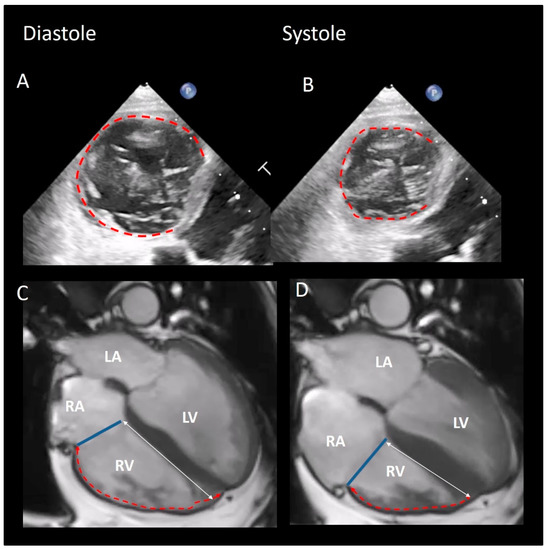

2.2. CMR

2.3. Echocardiography

5. Physiological and Physiopathologic Consequences of the Annular Structure

6. How Many Leaflets Has the Valve?